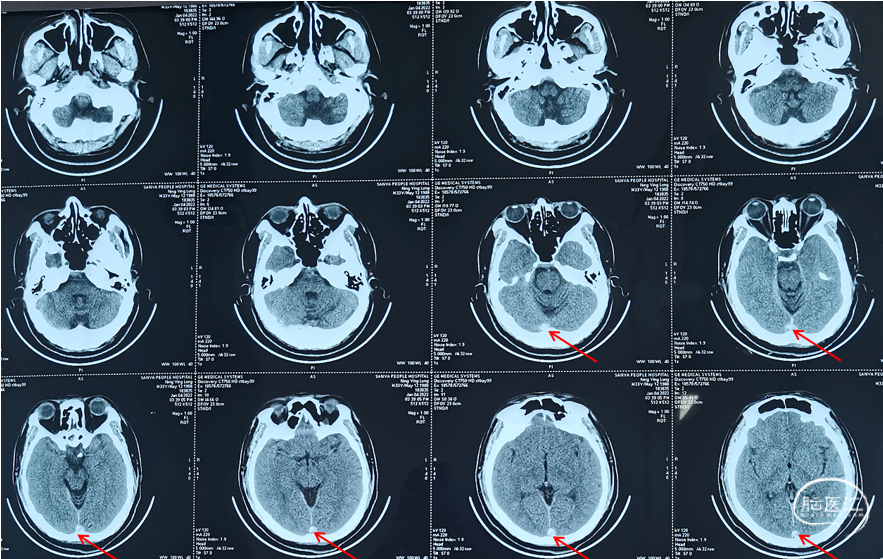

头颅CT(2022-1-4)

●头颅CT(2022-1-4,外院):上矢状窦、右侧横窦密度增高,可疑静脉窦血栓,建议MR平扫+MRV成像检查。

于1月3日患者出现阵发性头痛,伴恶心、呕吐,呕吐物为胃内容物,就诊于外院,查头颅CT示:上矢状窦、右侧横窦密度增高,考虑静脉窦血栓,建议患者住院治疗,后患者就诊于外院,行头颅核磁等检查,具体不详。